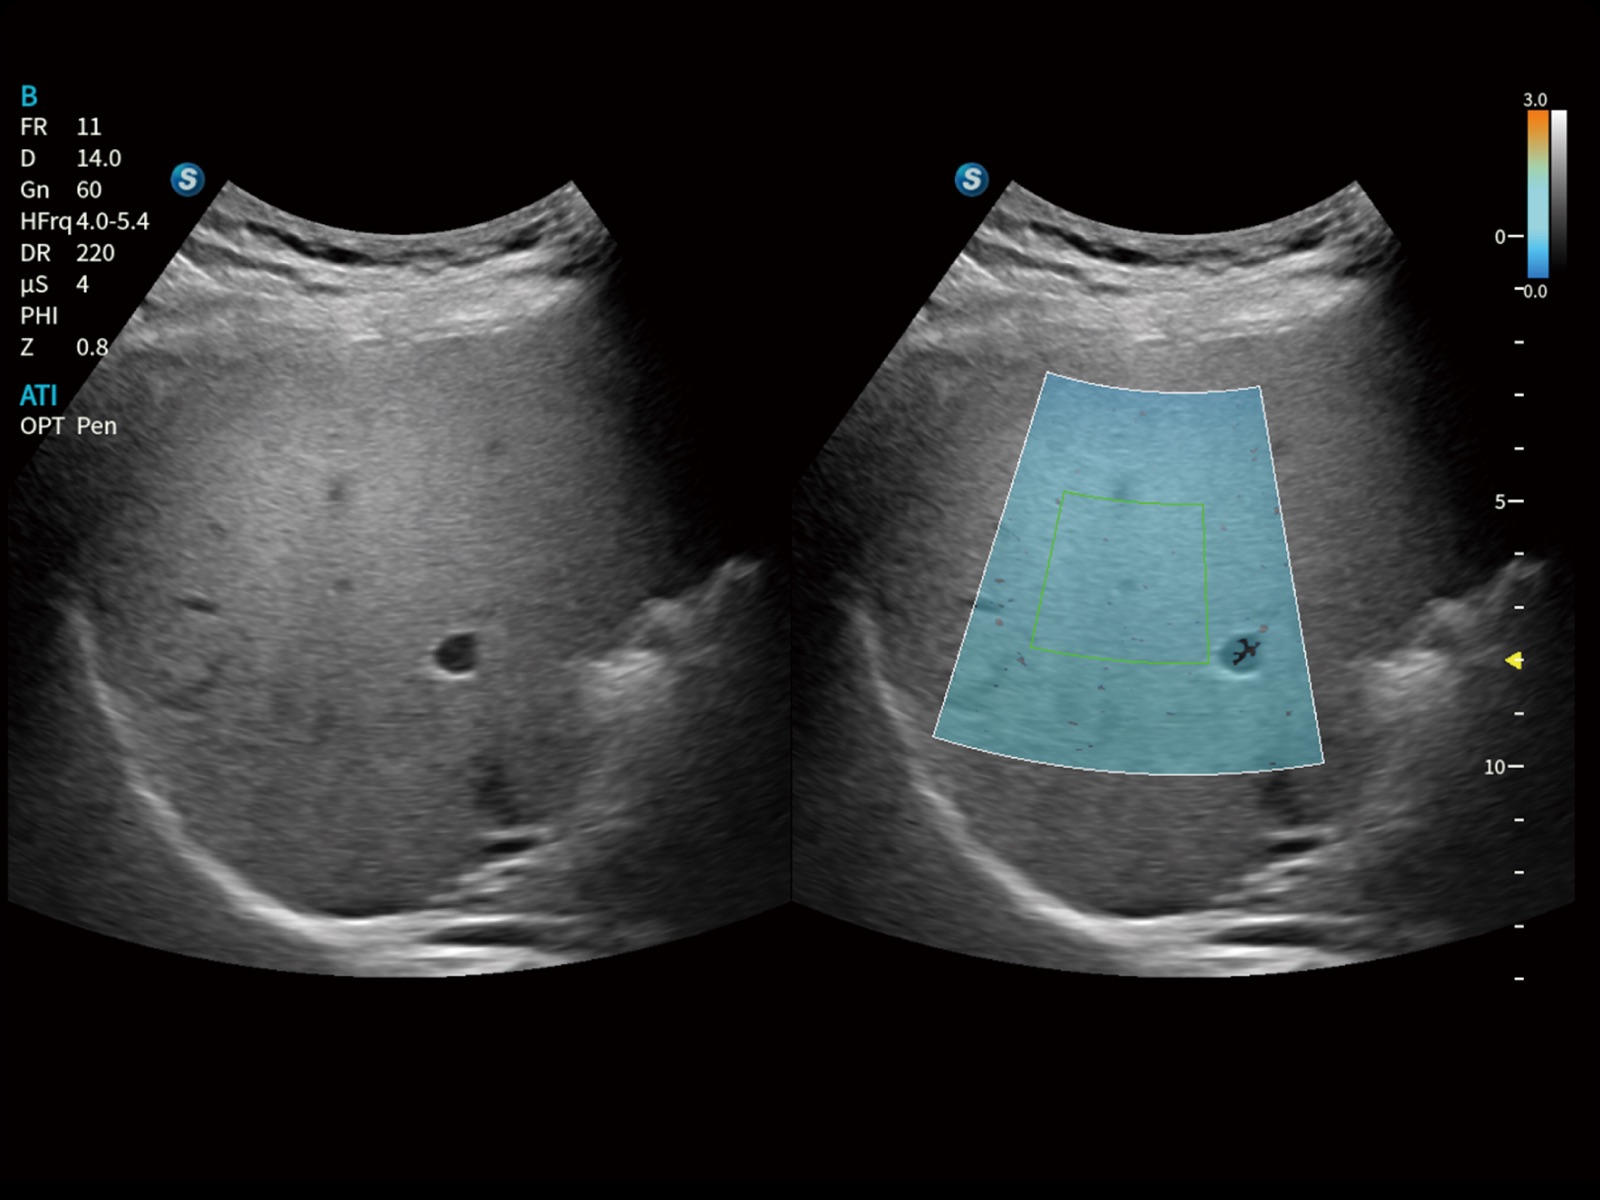

全身应用

专科应用